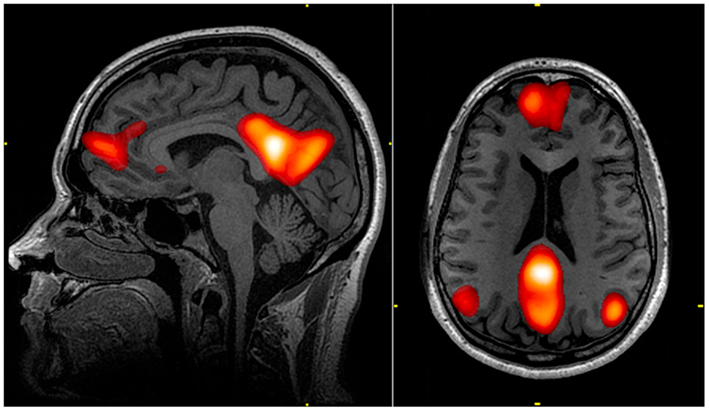

우리 뇌에는 디폴트 모드 네트워크(default mode network), 즉 DMN이라는 것이 존재한다.

디폴트 모드니까 멍때릴 때는 켜지고 업무나 운동 등 외부에 몰입거리가 있을 때는 꺼진다.

DMN이 켜져있을 때 우리의 뇌는 자신에 대한 생각으로 넘쳐나고 자아에 대한 의식들을 확립하게 된다.

주요 우울장애가 있던 환자들의 경우 저 DMN이 과도하게 활성화 되어있었다고 한다.